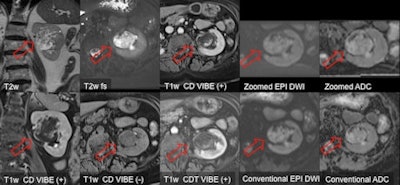

Other anatomical regions where this zoomed technique can lead to a clinical improvement include head and neck applications, other abdominal organs such as the kidneys, and also in the prostate, according to Haneder. If a biopsy is negative, despite high prostate-specific antigen (PSA) values and suspected prostate cancer, a multiparametric MR, including T2-weighted morphology, DWI, perfusion, and spectroscopy, is one route for detecting prostate cancer and guiding a further needle biopsy.

"Artifacts such as geometric distortion often hamper DWI of the prostate. In many cases, this can be solved by zoomed EPI-DWI for higher quality visualization; reduced geometric distortions allow an accurate fusion of functional DWI and morphology," he stated. "From a clinical point of view, this technique could and should become routine as a perfect MR detection tool for patients with high PSA values but negative biopsies."